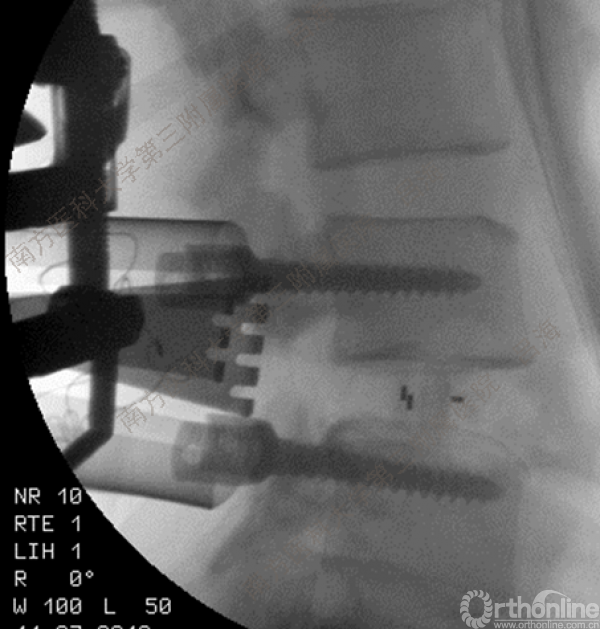

随着社会老龄化进程加快,胸腰椎退行性病变的治疗已经成为脊柱学术界的一个热点话题。MIS-TLIF手术可以治疗多种不同的胸腰椎退行性疾病,南方医科大学第三附属医院吕海教授结合病例为我们一一展示了该术式在治疗不同胸腰椎疾病时的具体手术过程。